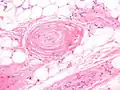

The cause is unknown.[1] It has all other features of a typical lipoma.[2]: 624 [3] When surgically removed, it appears yellow-red with a capsule.[1] Under the microscope, it features mature adipocytes and branching vessels of capillary size, which typically contain fibrin thrombi.[1]

Small vessels in adipose tissue The vessels typically contain hyaline or fibrin (pictured) thrombi[4]

The vessels typically contain hyaline or fibrin (pictured) thrombi[4]